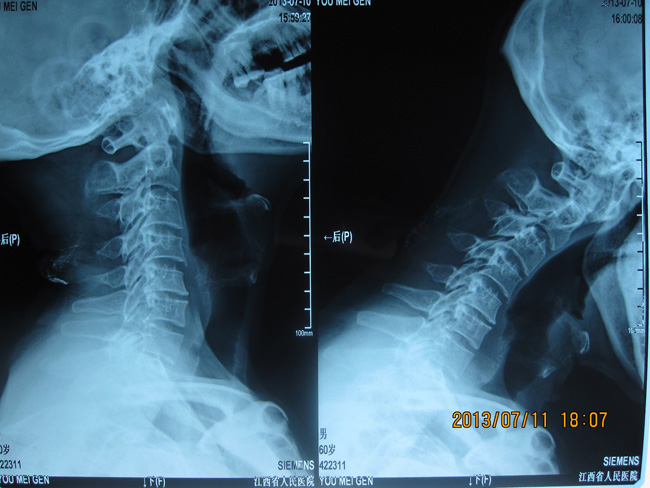

附:寰枢椎手术病例图片一

过伸位(复位) 过屈位(脱位)

来自樟树的游梅根今年60岁,是骨二科39床患者,因颈部外伤后颈项部痛不适半年余入院。受伤后在当地医院和省内某大医院诊治,均认为是颈部软组织挫伤,给予药物治疗后症状却越发严重。后经亲戚介绍慕名找到江西省人民医院骨二科。我接诊患者后经过仔细检查,发现患者系合并椎动脉孔畸形的寰枢椎不稳。患者颈部前屈时寰枢椎脱位,后伸时寰枢椎又自然复位,故不易发现,CT还显示患者左侧椎动脉孔内挤高跨畸形。

患者需手术治疗,否则颈脊髓长时间受到脱位的压迫或刺激将导致高位颈髓病甚至瘫痪,而寰枢关节位于脊柱的最高点,作为生命中枢的延脊髓交界从寰枢关节经过,这样的解剖特点使寰枢椎手术有脊柱外科的“珠穆朗玛峰”之称,手术风险高,一旦出现操作失误或并发症,病人就可能高位截瘫,丧失呼吸功能,生命将难以维持。而该例患者还合并椎动脉畸形,术中误伤椎动脉的也是手术的危险因素之一。这样的手术对医生而言无疑是一项挑战。为慎重起见,做到术前心中有数,我多次到双源CT室调阅患者1mm薄层扫描重建CT片,研究椎板螺钉和椎弓根钉技术的可行性, 后提交科室讨论, 最终决定采用目前国内较先进的枢椎椎板螺钉技术(可以避开畸形的椎动脉)结合寰椎椎弓根螺钉技术进行寰枢椎复位固定植骨融合术。随着全麻成功实施,上颅骨牵引,摆体位,显露进针点,植入内固定,复位,取骨植骨,缝合。每一步都有条不紊地进行,每一步都胸有成竹地实施,手术历时3小时,出血约200ml,不用输血顺利完成。术后第4天患者即佩戴颈托下地活动,颈项部疼痛缓解,而术后12天就拆线出院了。